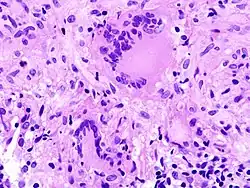

Kriterien der Malignität

- Makroskopisch: Infiltrierend/diffus wachsend

- Histologisch: Nekrosen, Kapillarisierung (Neoangiogenese), Aufhebung der normalen Histologie.

- Zytologisch: Polymorphie, basophiles Cytoplasma, erhöhte Kern/Plasmarelation

- Nukleär: Polymorphie, Polychromasie, Hyperchromasie, Aneuploidie, (vergrößerte) Nukleolen, vermehrt Mitosen, atypische Mitosen, erhöhter Proliferationsindex (Ki-67 = MIB-1).